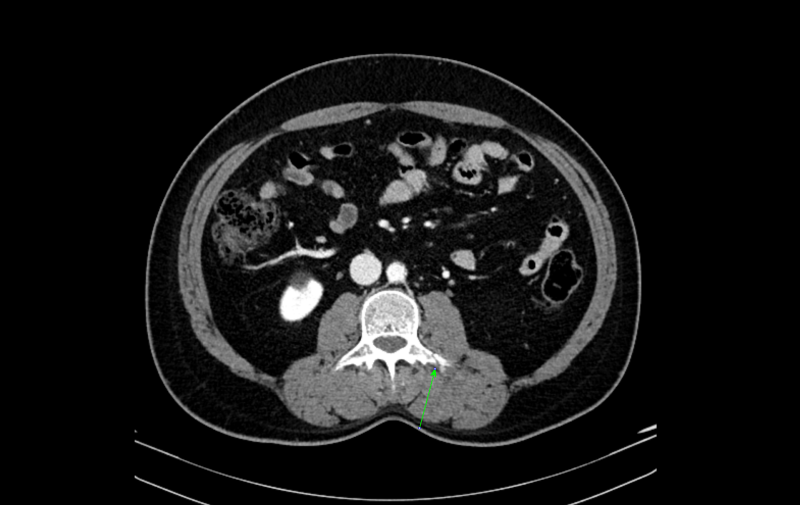

CT는 뼈의 내부 구조를 세밀하게 확인할 수 있어 미세 골절과 같은 확인이 용이하고 협착과 같은 질환을 파악하는 데 용이합니다.

교통사고로 인한 충격이 머리에 전달되고 두통, 어지럼증, 구토 등의 증상이 심하다면 뇌출혈 등을 가장 빠르고 쉽게 확인할 수 있는 CT 촬영도 큰 도움이 됩니다.

CT는 상대적으로 촬영 시간도 짧고 판독도 빠르게 진행할 수 있기 때문에 적절히 활용하면 매우 유용한 검사 방법입니다.